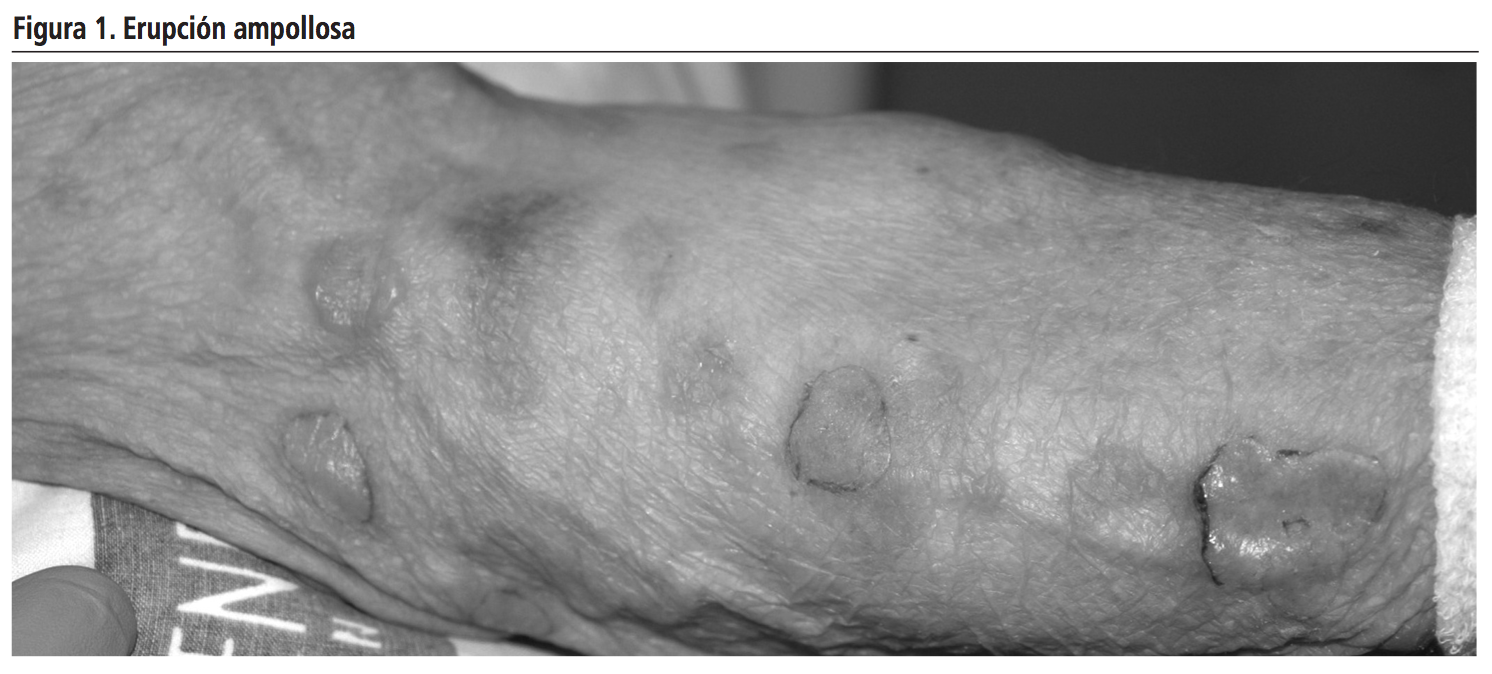

Tras diez días en tratamiento con vancomicina el paciente debutó con una erupción ampollosa generalizada que comenzó en la zona del periné, extendiéndose al resto del tronco y extremidades (Figura 1).

Presentó vesículas y ampollas tensas sobre base eritematosa, de contenido seroso y morfología anular o en “collar de perlas”, levemente pruriginosas, así como lesiones sangrantes en mucosa oral, iniciándose tratamiento tópico con pomada protectora y corticoides intravenosos. Ante sospecha de pénfigo y respuesta inadecuada al tratamiento, se derivó a Dermatología que ante sospecha de DAL, suspendió vancomicina y pautó curas con povidona yodada y mupirocina tópica (Figura 2). No aparecieron nuevas lesiones tras la retirada de vancomicina y se observó una desaparición paulatina de las existentes, dejando erosiones e hiperpigmentación residual.